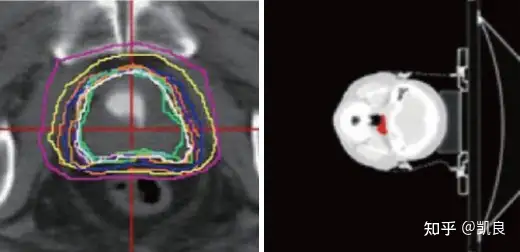

放射治疗前,医师需要勾画出恶性肿瘤和正常组织的范围,而此关键步骤的紧密产品质量关系到放射治疗产品质量。现阶段的方案一般都是由医师纯手工勾画,勾画标准比较随便,相同的医师之间勾画的结论差异较大,为最后的结论增加了很多不稳定性。应用领域广度学习演算法对 CT/MRI 双逻辑系统影像进行处理,较好的解决了现阶段的问题,精确度能达至医师勾画水平。

纯手工描画Bellary(左)和AI描画Bellary(右)二、农业: